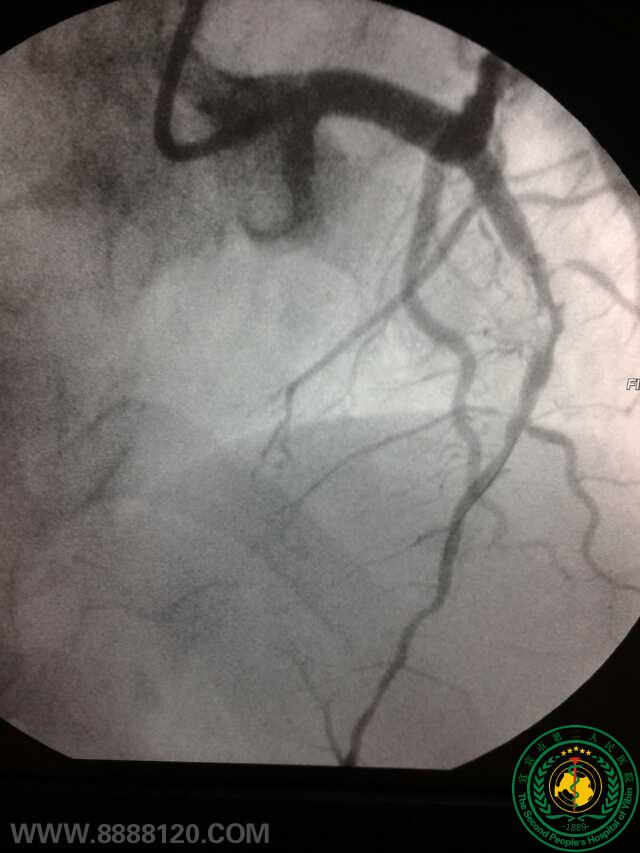

冠脉治疗新技术——宜宾首例冠脉旋磨术

冠脉治疗新技术——宜宾首例冠脉旋磨术6773

宜宾市第二人民医院 图文